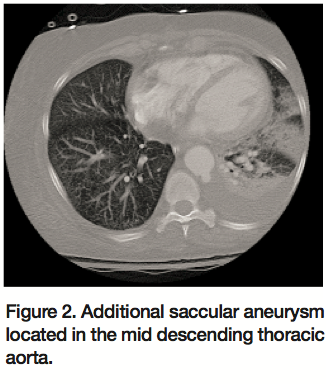

The patient is a 67-year-old African American female with a past medical history significant for chronic obstructing pulmonary disease, hypertension, and deep vein thrombosis with pulmonary embolism who was transferred to our institution for evaluation of repair of an aneurysm of the ascending aorta and transverse arch of the aorta. She had undergone an open repair of an acutely symptomatic abdominal aortic aneurysm 3 months prior. The patient was admitted to an outside facility due to severe flank pain; imaging at that time showed an acute increase in the size of her aortic arch to 7.4 x 6.7 cm. Repeat imaging at our institution showed the aneurysm to have further increased in size to 8 cm with surrounding hematoma; therefore, a diagnosis of contained rupture of the aneurysm was made (Figures 1 and 2). Preoperative angiogram demonstrated the 8 cm aortic arch aneurysm (Figure 3) as well as a second saccular aneurysm located in the mid thoracic aorta. Owing to the patient’s multiple comorbidities, the decision was made to repair the aneurysms endovascularly to prevent exsanguination and death.

Attention was then turned to a second saccular aneurysm located in the mid thoracic aorta. The native aorta measured about 28 mm at this site. In order to avoid covering excessive length of the descending thoracic aorta, a 32 x 32 x 48 mm Talent thoracic distal main extension endograft was used (Figure 7).